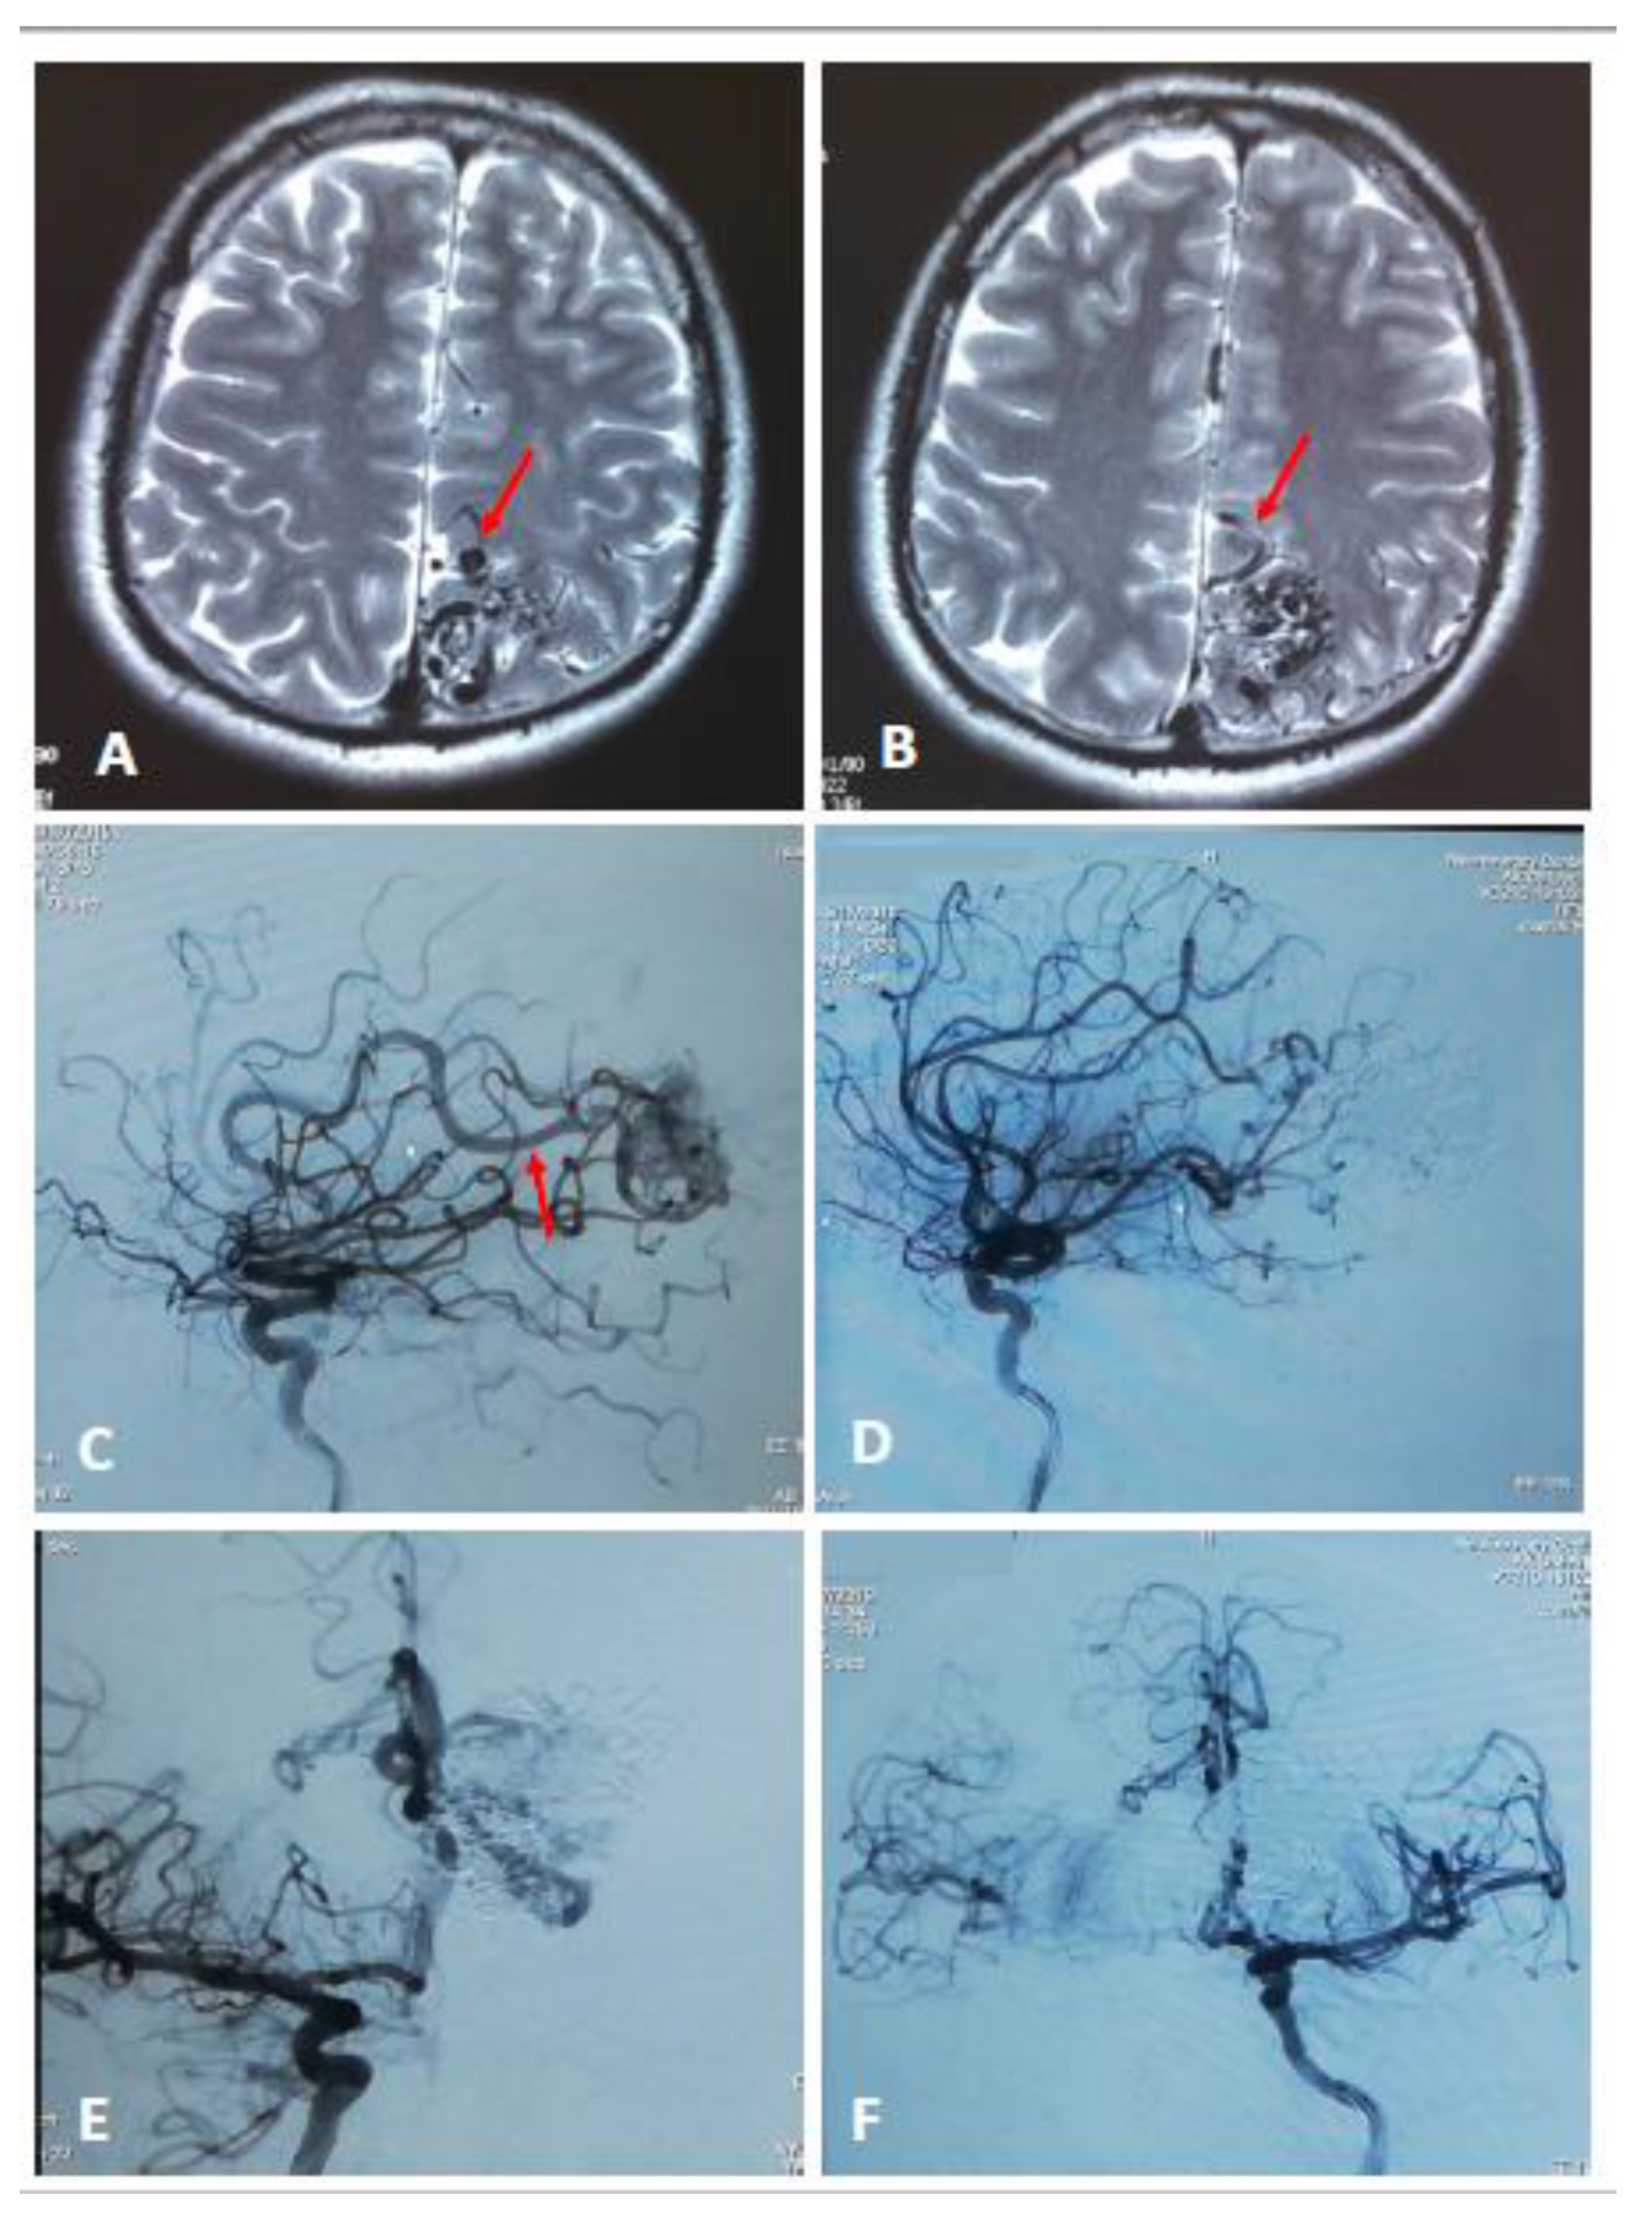

The main criteria for embolization were the following angiographic findings: a direct AV fistula within the AVM, dilated varix, and afferent artery with a diameter 2–3 times wider than the arteries supplying this region of the brain (Figure 2). The brain AVMs not eligible for neurosurgical intervention according to the results of angiography were kept under clinical observation.

Figure 2.

Axial MRI of grade 3 brain AVM demonstrates varix (A, red arrow) and dilated afferent vessel (B, red arrow). Lateral view angiogram demonstrates dilated afferent artery before embolization (C, red arrow) and after (D). Anterior-posterior view angiogram before total embolization (E) and after (F).